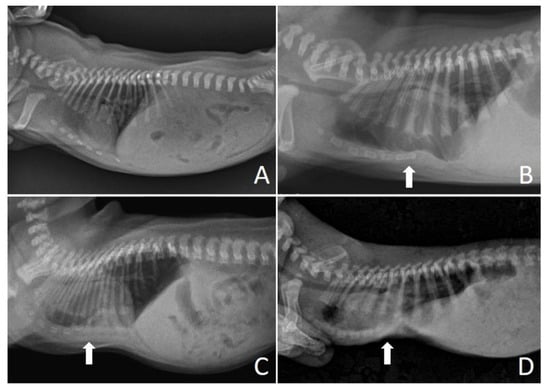

On the chest X-ray (Figure 3), it was possible to observe the ventrodorsal deviation of the sternum in the medial and caudal region of the ventral thorax, diagnosing pectus excavatum. The frontosaginal and vertebral index corresponded to 1.8 cm (≤2.0 cm) and 10.2 cm (>9 cm), respectively, classifying the pectus as mild grade. In addition, cardiopulmonary alterations were found: pneumonia with alveolar pulmonary pattern, pulmonary hyperinflation, rounded cardiac silhouette (globose aspect) and cardiac deviation to the left.

Figure 3.

Chest X-ray. (A) Right side position and (B) left side position, demonstrating ventrodorsal deviation of the sternum bone (arrows); (C) Ventrodorsal position demonstrating narrowing of the thorax (arrows), pneumonia and left cardiac deviation.

Figure 4 shows the chest X-ray of a neonate of the same litter, without thoracic alterations, to compare chest structures and aid in diagnosis.

Figure 4.

Normal thoracic radiographic examination. (A) Right side position; (B) Left side position; (C) Ventrodorsal position.